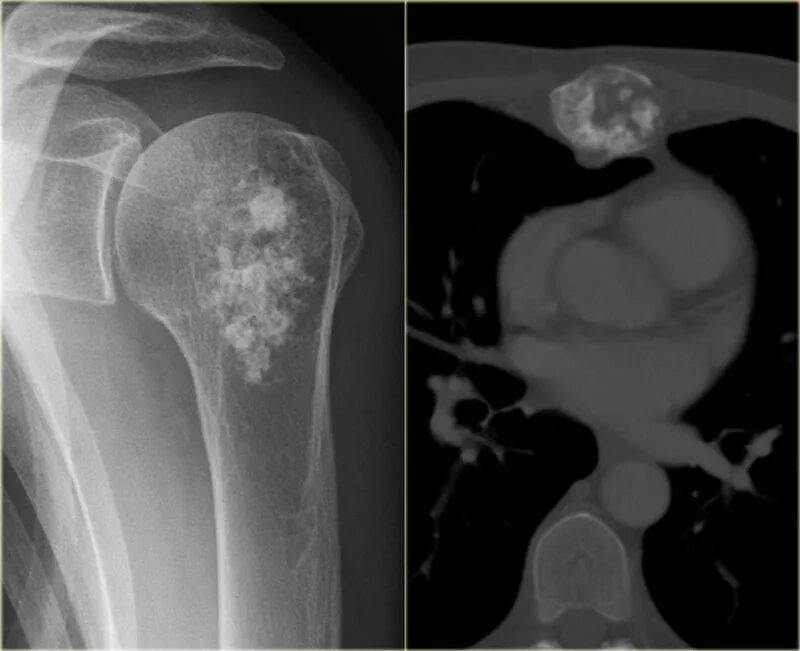

Метастазы в тазобедренном